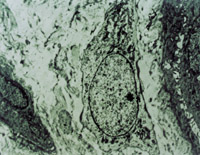

原位切取创面组织病理切片检查,见坏死上皮组织间有大量颗粒样组织,新生上皮细胞和胶原纤维组织呈团样增生,并可见到典型的类似于胎儿皮肤结构的皮肤胚胎基(embryonic base,EB)(图5-3-4a,5-3-4b)。MEBT治疗10天后,在创面边缘取上皮组织病理切片可见到较原始的上皮组织。

5-3-4a 新生上皮组织和胶原纤维增生,可见典型EB(皮肤胚胎基) HE×40

5-3-4b 新生上皮组织中可见微血管,胶原纤维和上皮细胞(干细胞)形成的皮肤胚胎基组织 HE×40